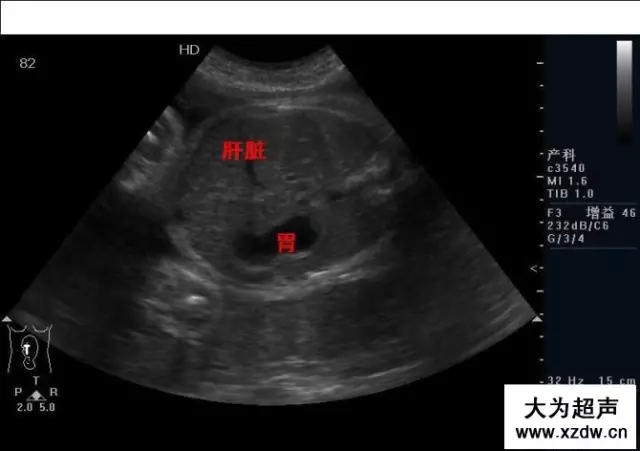

產(chǎn)科超聲正常圖片